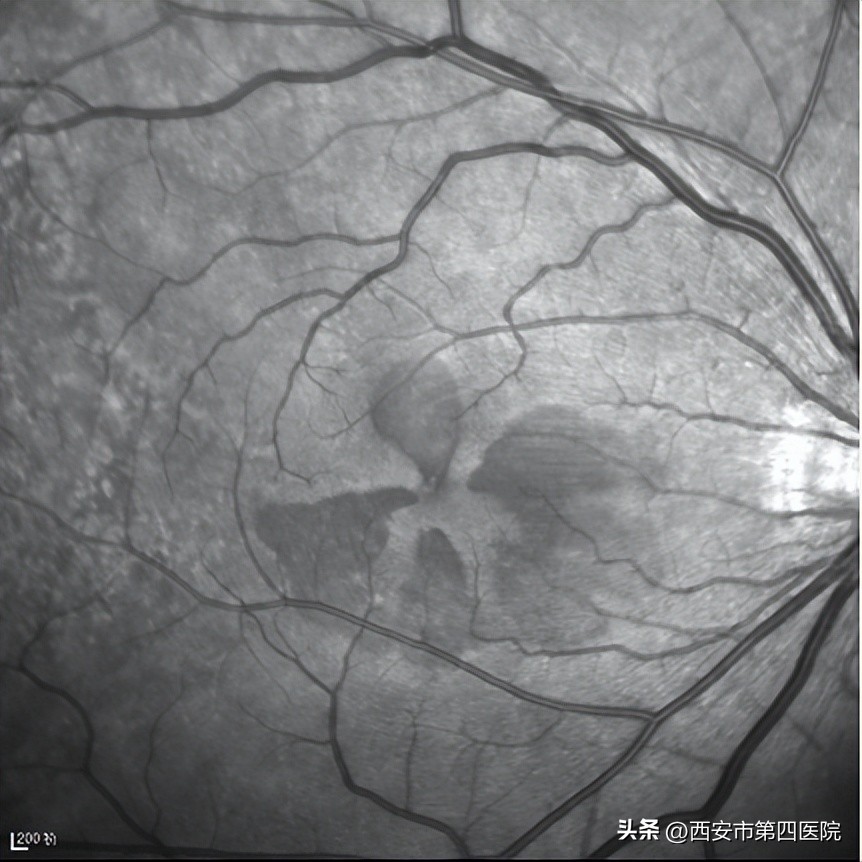

王海燕主任立即安排患者做了检查,患者右眼视力0.6,左眼视力1.0,眼压正常,眼底检查和红外(IR)成像发现双眼眼底有“花瓣状”暗红色病灶,尖端指向中心凹

双眼红外(IR)成像:所示黄斑区可见“花瓣状”低反射信号,尖端指向中心凹)